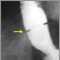

Schatzki ring - X-ray

A lower esophageal ring is an abnormal ring of tissue that forms where the esophagus (the tube from the mouth to the stomach) and stomach meet.